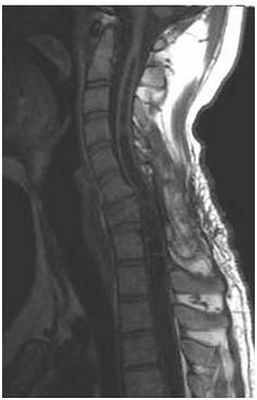

МРТ изображение (T1-взвешенное изображение) пациента с тяжелым повреждением спинного мозга и шейного отдела позвоночника (С7) в результате «травмы ныряльщика». Обратите внимание на полость (темная полоска в середине спинного мозга), которая простирается кверху и книзу от уровня повреждения. Сразу после травмы у пациента развилась слабость в ногах, а впоследствии возникла слабость в руках из-за сирингомиелии.